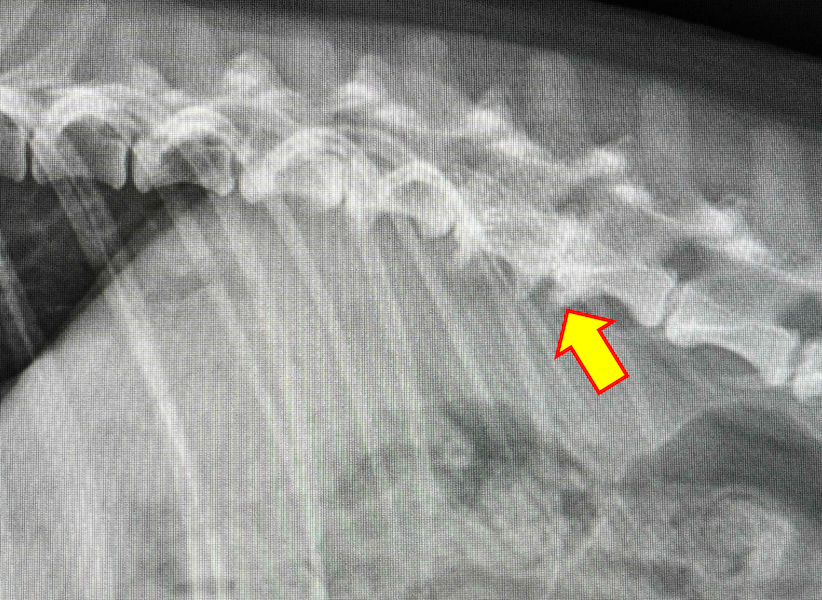

変形性脊椎症は、身体を支えている背骨(脊椎)が年齢とともに少しずつ変形してしまう病気です。多くは無症状なためレントゲン検査で偶然見つかることも珍しくありません。しかし、変形した脊椎が神経を圧迫することで痛みや歩行異常が現れることがあります。椎間板の変性や加齢による椎体間の不安定性が原因と考えられています。症状が見られる場合は、鎮痛剤で痛みを和らげたり、温熱療法などの理学療法で筋肉の緊張をほぐしながら経過を見ていきます。最近活動量が減ってきた、歩きにくそうにしている、などの変化は病気のサインかもしれません。なにか気になる症状があればお気軽にご相談下さい。

変形性脊椎症とは身体の構造を支えている脊椎に変形が起こってしまう病気です。多くは無症状で健康診断などで偶発的に発見される事があります。しかし変形した脊椎が神経を圧迫する事でまれに痛みや運動障害を引き起こす事があります。治療は症状がある場合は鎮痛剤の投与や、温熱治療などの理学療法を行って痛みを緩和していきます。また肥満の場合には脊椎に過度な負荷をかけてしまうため、適切な体重管理が重要となります。お家のわんちゃんが高齢になって活動性が落ちてきた、歩きにくそうにしているなど気になる症状がありましたら、お気軽にご相談ください。

脊椎に骨増殖と呼ばれる変形が起きる疾患で、加齢に伴い発症率は上昇します。多くは無症状ですが、一部は慢性的な痛みを生じて日常生活に支障を来たすこともあります。持続的な脊椎への負担や椎間板の変性などが原因と考えられており、痛みがある際には消炎鎮痛剤の内服や運動制限、温熱療法などの治療が推奨されます。動きが鈍い、歩きづらそうなどの症状がある場合にはお早めにご相談下さい。